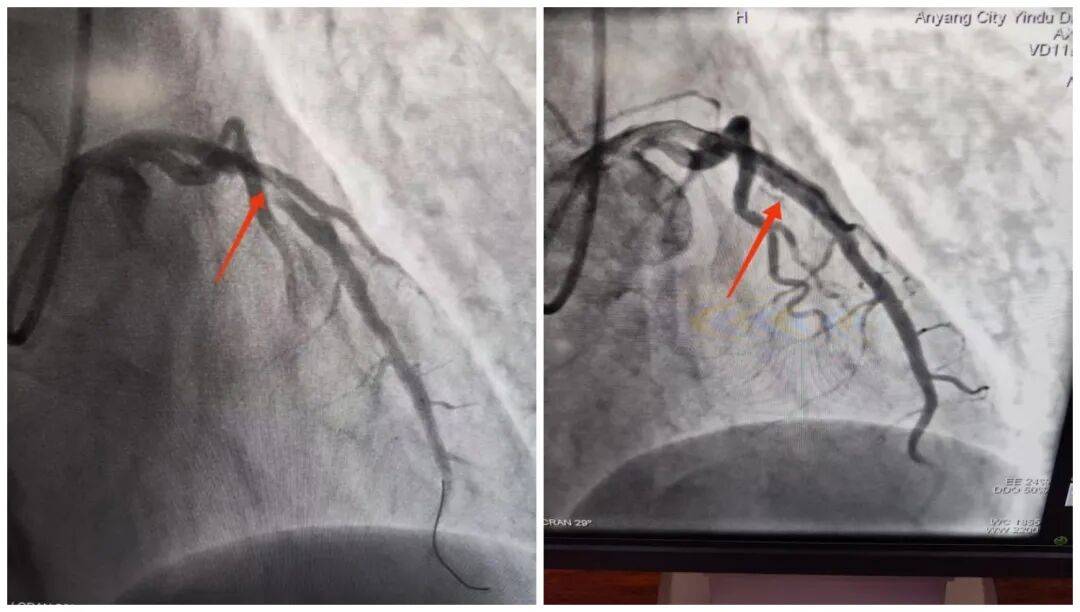

14:54,承載著生命希望的救護車抵達殷都區人民醫院大門口。14:56,劉大爺被推至導管室門口,早已等候在此的醫護團隊立即上前,無縫銜接將劉大爺推進導管室,手術隨即開始。15:18,醫院介入團隊精準操作,治療導絲成功通過病變部位,血管開通的關鍵一步順利完成。15:50,手術圓滿結束,成功挽救了瀕臨壞死的心肌。從劉大爺到達殷都區人民醫院門口到成功開通堵塞血管,整個過程僅用了24分鐘,這一速度遠優于國際通行的90分鐘黃金標準。

此次對劉大爺的成功救治,并非偶然,而是“心電一張網”打破診療壁壘、實現雙院高效聯動的生動實踐。曲溝衛生院作為基層網絡醫院,在救治初期快速完成基礎檢查與初步處置,為后續治療“打底”;殷都區人民醫院專業團隊則憑借精湛技術和高效協作,精準“接力”,確保救治方案快速落地、手術順利推進。兩者緊密配合,真正打通了轄區內急性胸痛患者的分級救治綠色通道,為群眾的生命健康筑起了一道堅實的“防護墻”。